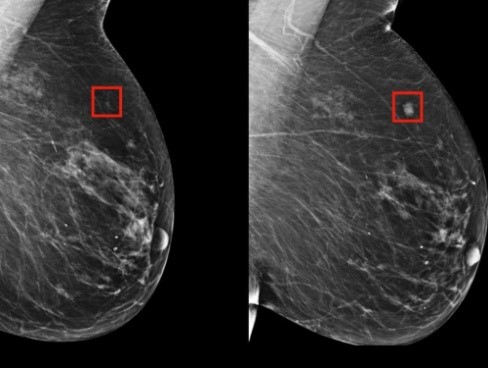

IA-CAD: Early Diagnosis Support for Breast Cancer

This project aims to develop an effective CAD system using deep learning to support early breast cancer diagnosis.